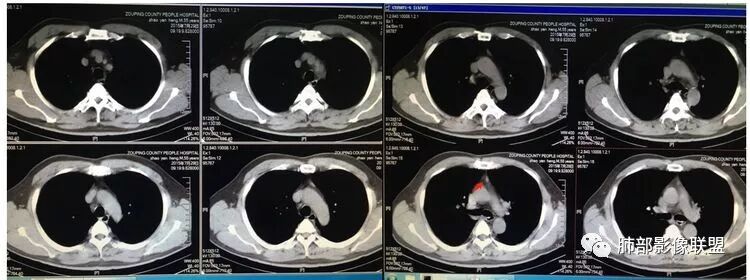

15年这个是原来的病灶吗?

还是后来新发的病灶?

感觉是

同一个部位

就是还是原来的病灶进展

应该是原有部位的进一步发展,

胸腺区小高密度灶,梭形

边缘张力不高

南边:

因为原病灶没看到,现在原有位置有一大病灶,如果是新发的,原有病灶会推移一边,但是没看到,倾向于原病灶增大

根据强化,高的70HU,低的没测,考虑囊实性

实性部分明显强

偏一侧

上面来的血供,病灶深分叶

附近心包似乎也不干净

有淋巴结

从前后变化,病灶的形态、强化、附近的淋巴结、心包改变,支持恶性

这图看起来有结节感